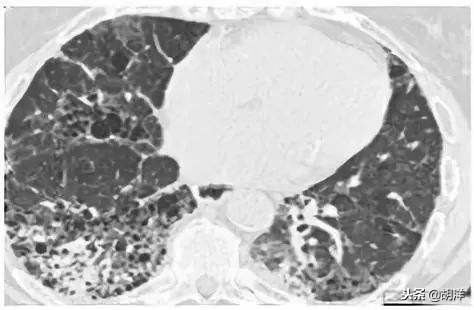

另外一大群间质性肺病为风湿免疫性疾病引起的间质性肺病,风湿免疫性疾病是一大类自身免疫系统侵犯自身组织引起的疾病,包括风湿性关节炎,系统性硬化症,系统性红斑狼疮,肌炎皮肌炎以及干燥综合症等,这些疾病通常会引起一系列肺部以外的症状,包括关节炎,皮疹,手指头皲裂,嘴巴干及眼干等症状,肺也是自身免疫性系统失去控制后常侵犯的器官,典型的改变就是间质性肺病,在胸部CT上的表现和特发性间质性肺炎类似,但治疗上有一定的不同,风湿免疫性疾病所致的间质性肺病除了可以使用激素治疗之外,还可以加用免疫抑制药物治疗,通常效果可,大部分可以长期生存。